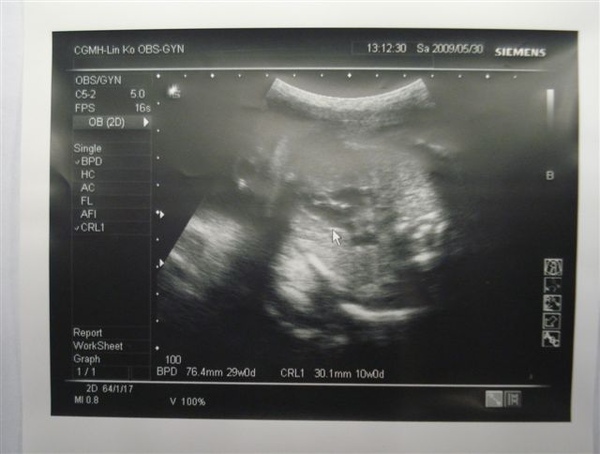

2009-05-30-第三十一週產檢(身長40cm、體重1600公克)